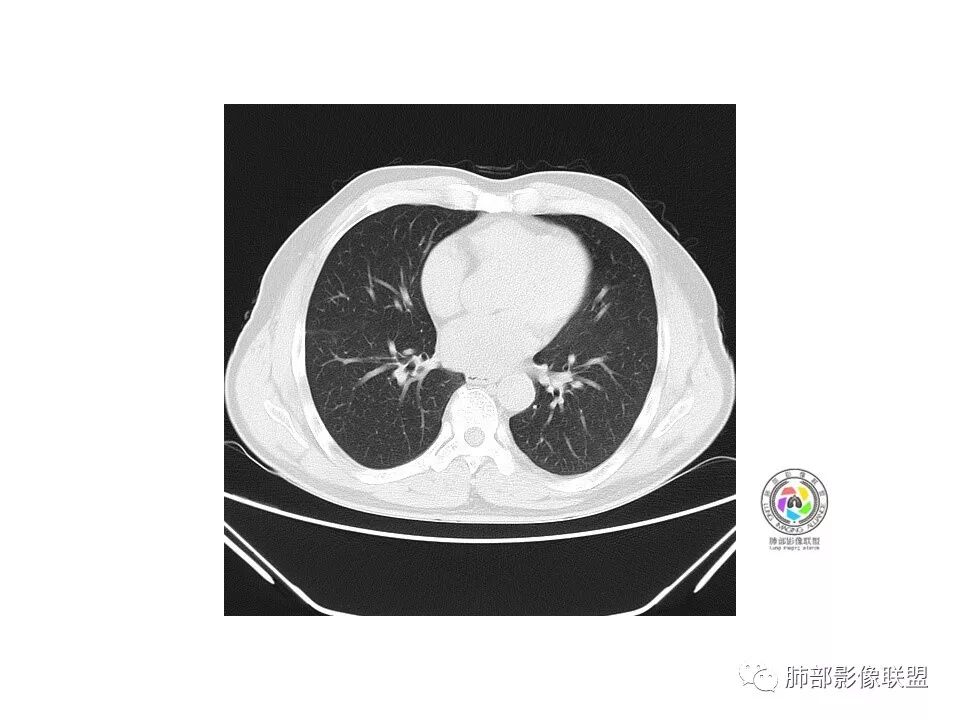

右肺下叶磨玻璃影,边界似清非清(考虑部分为血管断面围绕),周边见条索灶,胸膜牵拉弱。我把炎症放前面,建议抗炎治疗后复查除外恶性。

老年男性,右肺下叶前基底段GGN,界清,内部血管结构杂乱,叶间胸膜牵拉。考虑恶性,早期腺癌可能,建议抗炎治疗后复查对比。

右肺下叶前基底段见一磨玻璃结节影,呈分叶状,边缘部分模糊,与胸膜间有长条索粘连,内有增粗的血管影,后者边缘毛糙,考虑微浸润性腺癌,建议抗炎治疗后复查

老年男性,右肺下叶前基底段斜裂旁可见单个混合型磨玻璃结节mGGN,边缘清,内部结构紊乱,进入的血管增粗,支气管关系不好判断,斜裂侧可见牵拉,常规考虑微侵腺癌MIA,建议先抗炎后复查及手术干预。

老年男性,咳嗽咳痰3天。MGGN,边缘见月牙铲、胸膜牵拉,血管移动联通?冠状位隐约可见支气管穿行,考虑MIA,重建冠位可见结节比较靠近叶裂,可积极手术处理。

老年男性,右S8混合磨玻璃结节,边缘尚清晰,局部凹陷,叶间胸膜牵拉,考虑MIA可能大,建议抗炎治疗10天,6-8周后复查

右肺下叶混合磨玻璃密度结节,有月牙铲,内可见血管,血管移动联通,常规消炎复查,还存在考虑AIS-MIA

患者老年男性,右下肺前基底段靠近胸膜侧可见一个mGGO结节,边缘清淅,可见分叶征及月牙铲,小结节病灶胸膜牵拉明显,首先考虑MIA可能性大。

右肺下叶mGGO,边缘清晰,浅分叶,内血管影增粗,见点状实性成分,小支气管牵拉扩张,考虑MIA,建议抗炎后复查。

右肺下叶前基底段mGGN,边界清晰,内部结构杂乱,见网格空泡感,月牙铲,浅分叶及胸膜牵拉,倾向MIA。

右肺下叶GGO,边缘清晰,有月牙铲,有血管进入,内部结构紊乱,胸膜牵拉,考虑MIA,常规建议抗炎治疗后复查。

右肺下叶磨玻璃结节,边界清晰,边缘有分叶及月牙铲,并可见轻度胸膜牵拉,收缩力弱,有血管移动联通征,而且病灶内血管影轻度增粗,实性成分很少,考虑AIS,可以让子弹再飞一会,或常规抗炎治疗后复查。

界清ggo,月牙铲,考虑腺癌

右肺下叶前基底段磨玻璃小结节,其内血管稍增粗,边缘见分叶、月牙铲,考虑ais,炎性结节不排